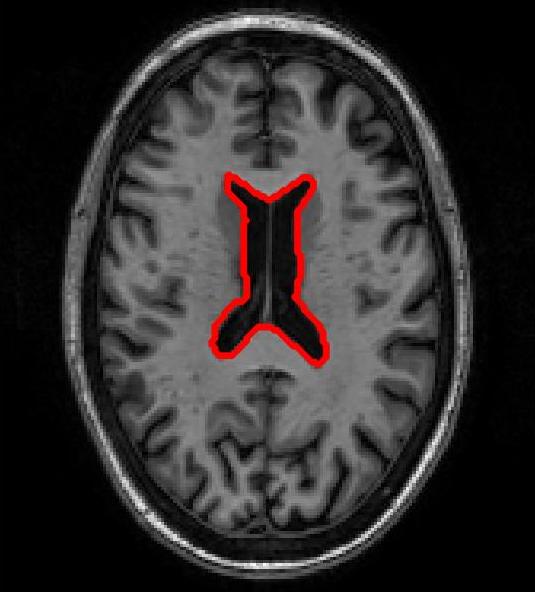

FigureΒ 3 shows results for brain image registration. We show the reference image in FigureΒ 3 (a) followed by an example floating image in FigureΒ 3 (b). The ventricle structure to be aligned is shown in red in both images. FigureΒ 3 (c)-(e) shows the deformed structures obtained by applying the registration field obtained from different methods to the floating image and superimposing these structures on the atlas image. The deformed structures from the floating image are shown in blue. In case of perfect registration the blue and red contours should coincide. In this case SR-Net actually does better than VoxelMorph, while SR-Net does significantly worse due to absence of segmentation information.

![]() |

| (a) | (b) | (c) | (d) | (e) |